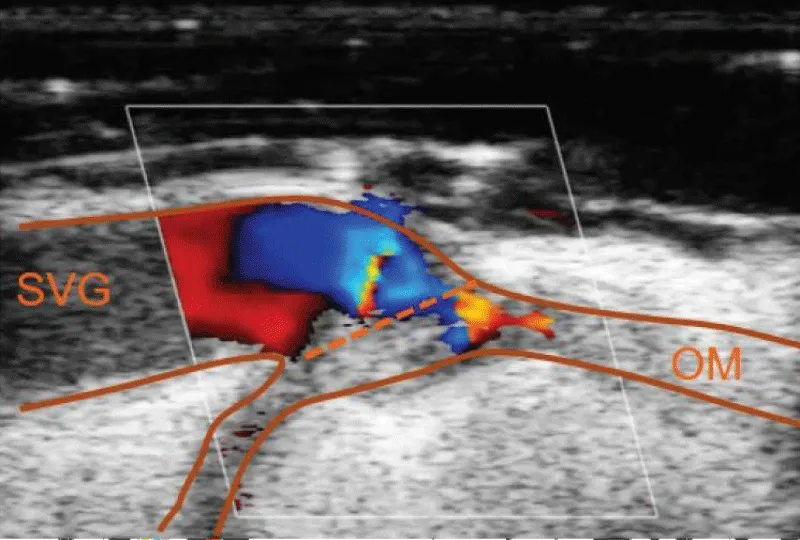

In case of obtaining dissenting values in comparison to the ideal measurement parameters or in case of doubt of the quality of the anastomosis performed, the epicardic echography presents as a valuable tool to provide a visual evaluation of the anastomosis, and sole the doubts (Figure 18).

Figure 18: Image of verification of an anastomosis between saphenous vein and marginal obtuse coronary artery, with Doppler echography, showing a decrease in the flow through the anastomosis due to the presence of a flap of the venous graft.